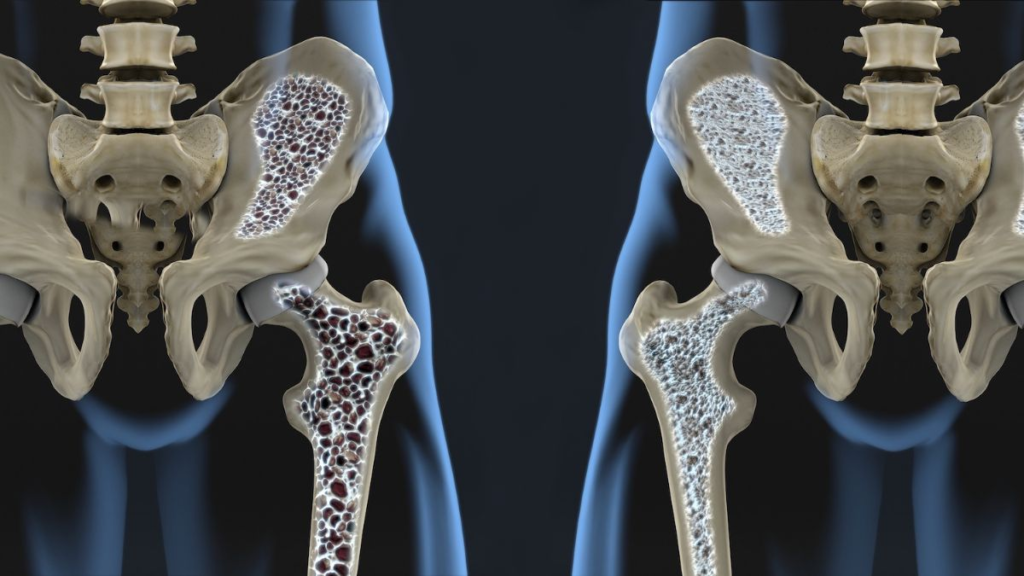

a bunch of adults, especially those over 40, are beginning to worry about calcium deficiency, osteoporosis, or the risk of fractures. This is where supplements like , like Osteopur enter the conversation.Osteopur is commonly marketed as a bone support formula designed to improve bone density, increase calcium absorption, and strengthen the skeletal system. Seriously, But what makes it different?

Like, a bunch of people , people ignore bone health until , until a fracture or severe , severe joint pain occurs. But bones are living tissues that are constantly rebuilding themselves. Guess , Guess what? After the age of 30, bone loss may gradually exceed bone formation.

And oh yeah, The silent problem: bone loss

One of the biggest challenges is that bone loss happens silently. You know what? You may not experience symptoms until the damage is extensive. Like, Conditions such as osteoporosis often develop slowly , slowly over years.